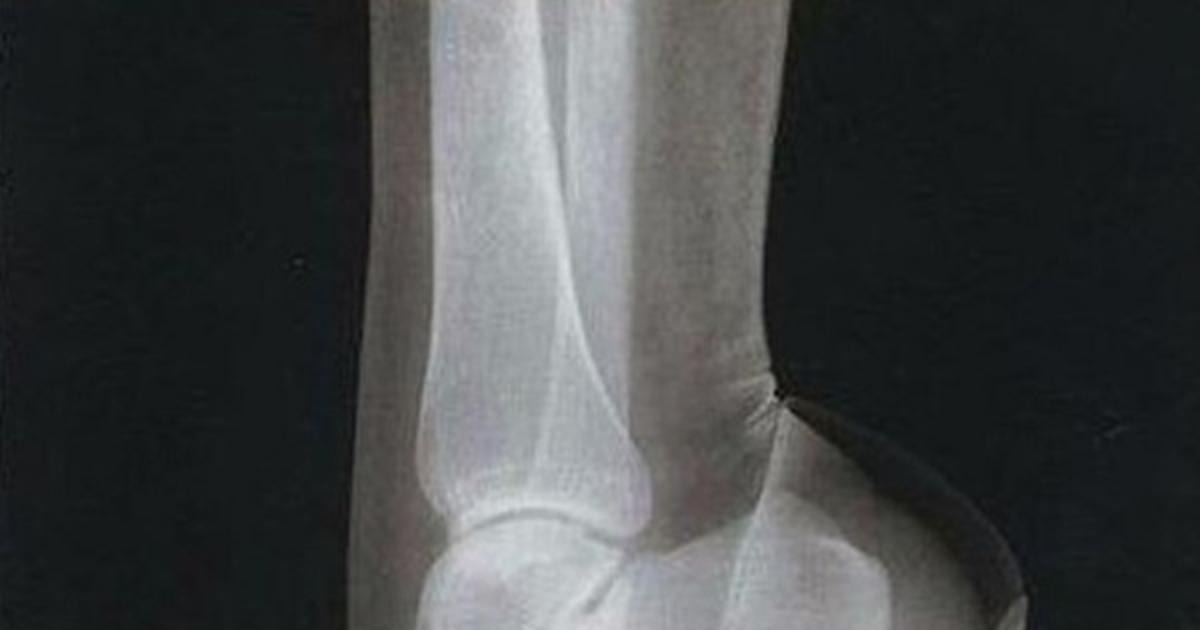

femme, Chaussures, commodité

femme

chaussures

commodité